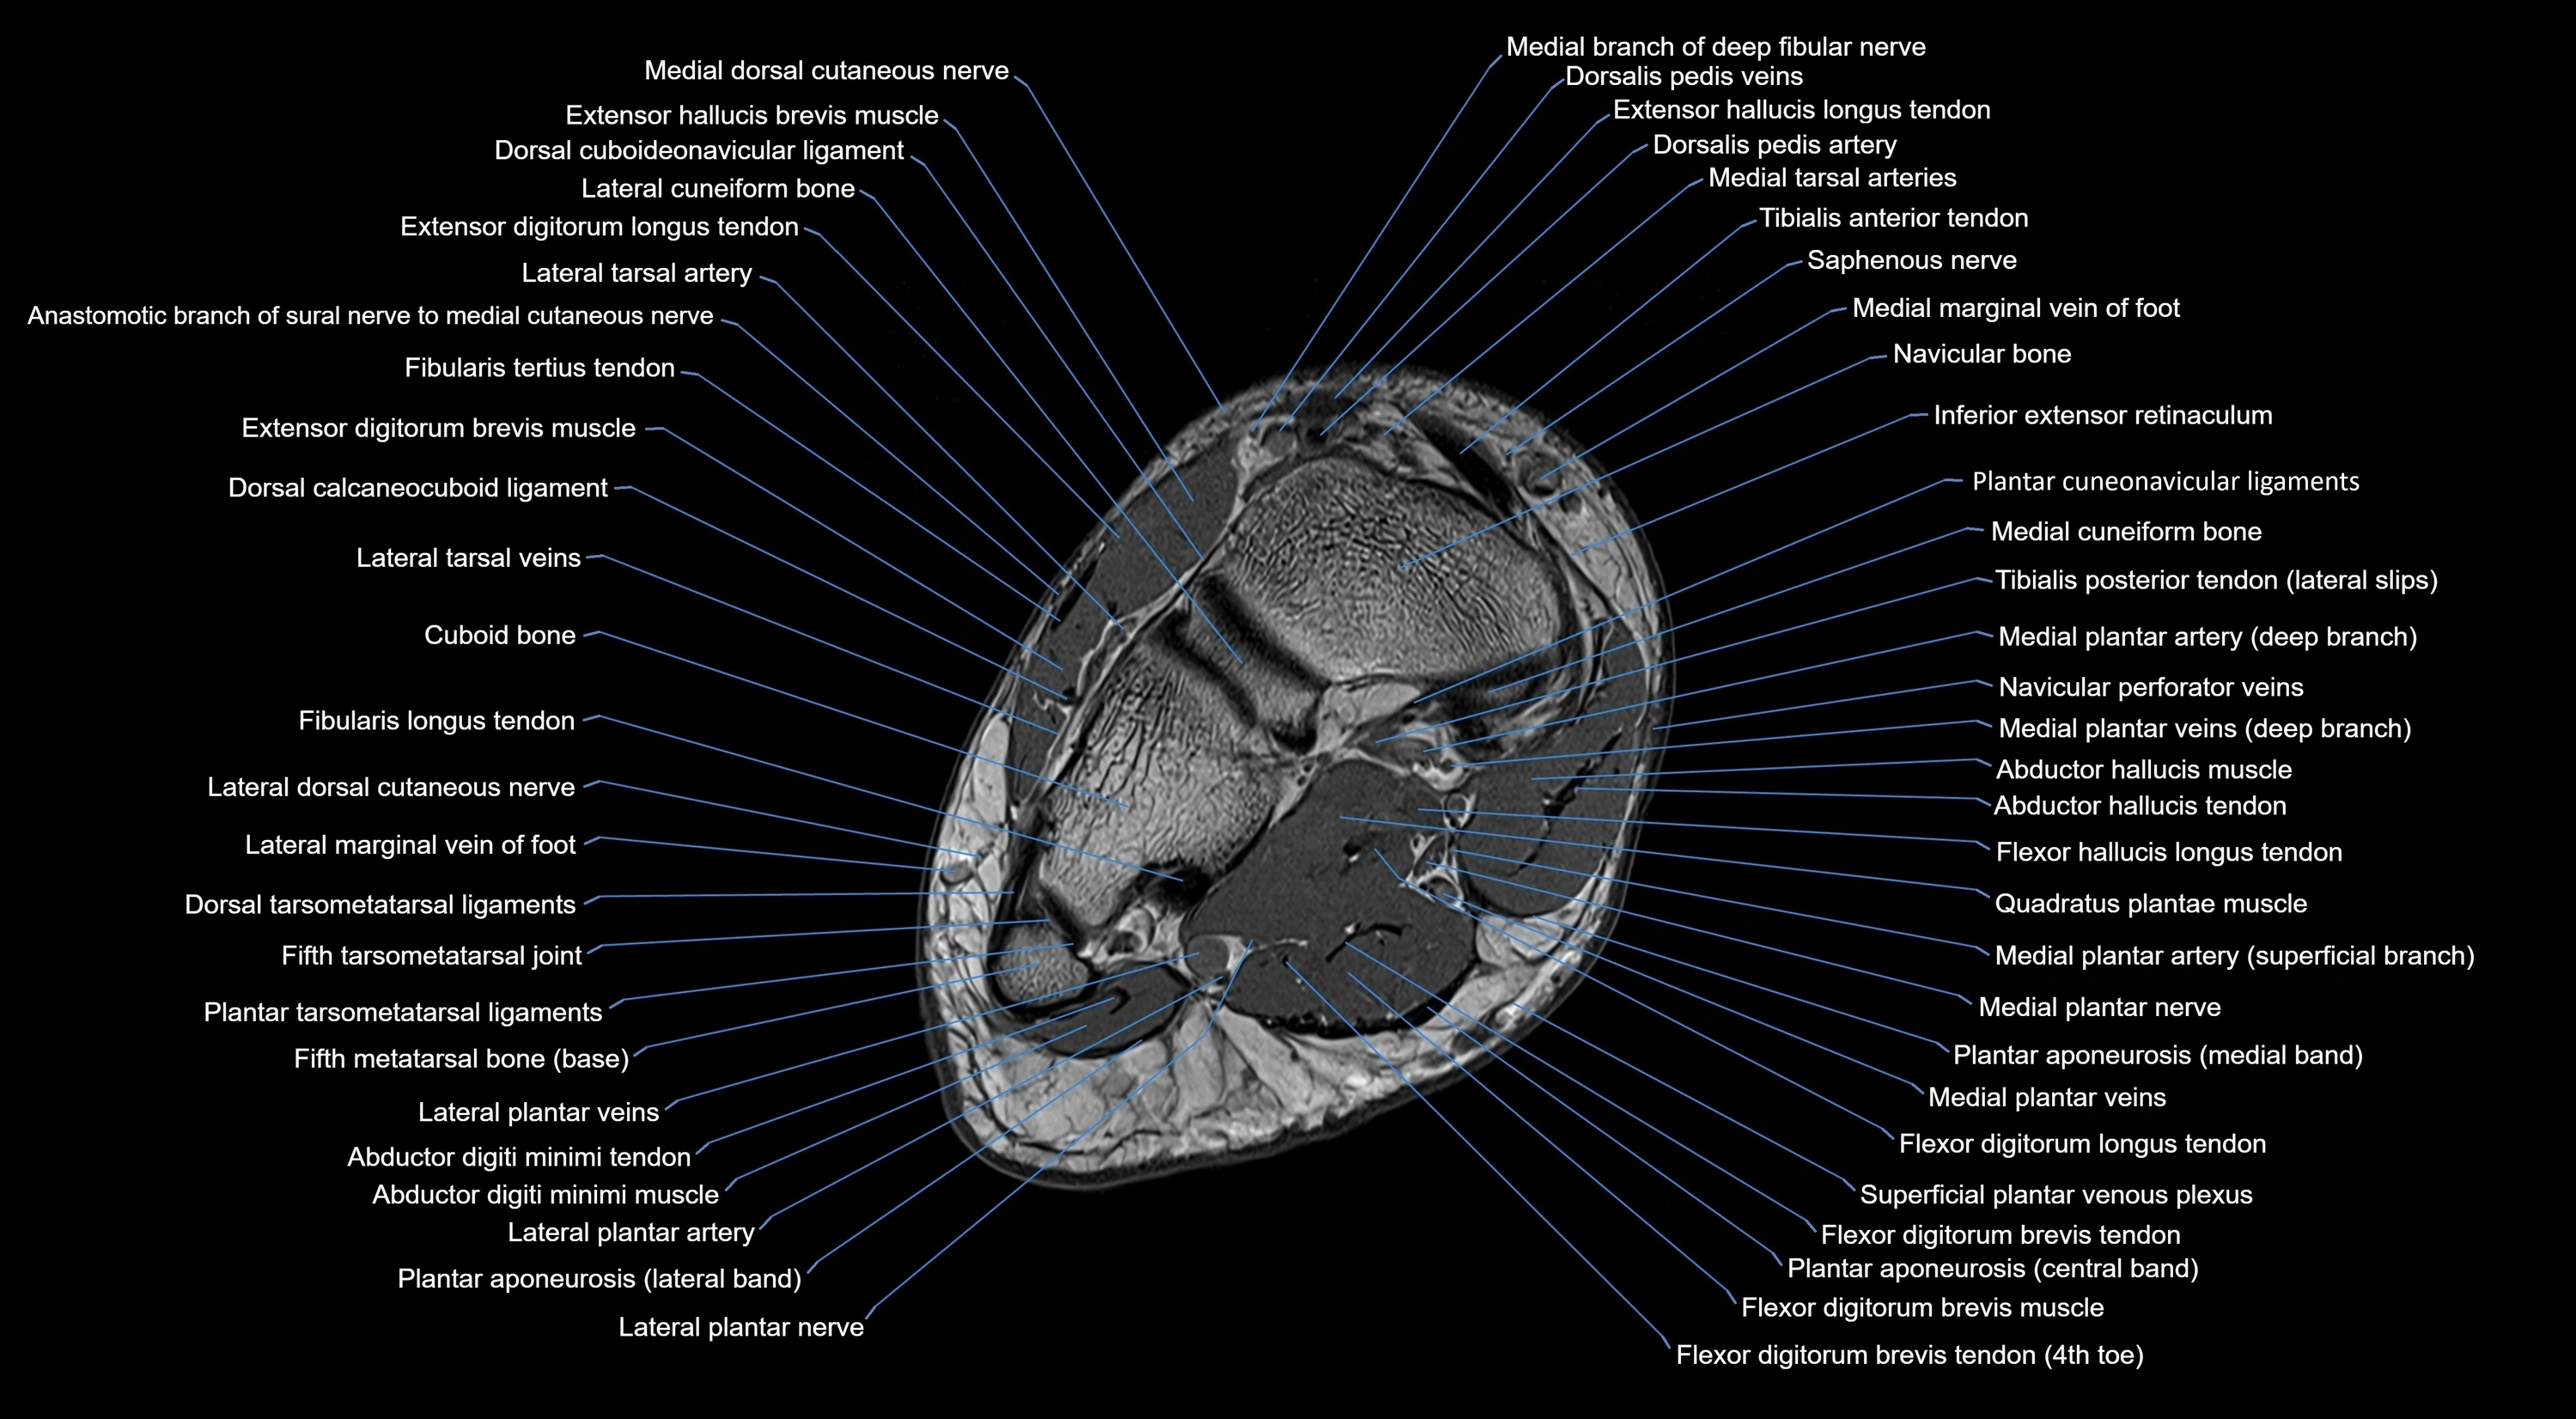

MRI image